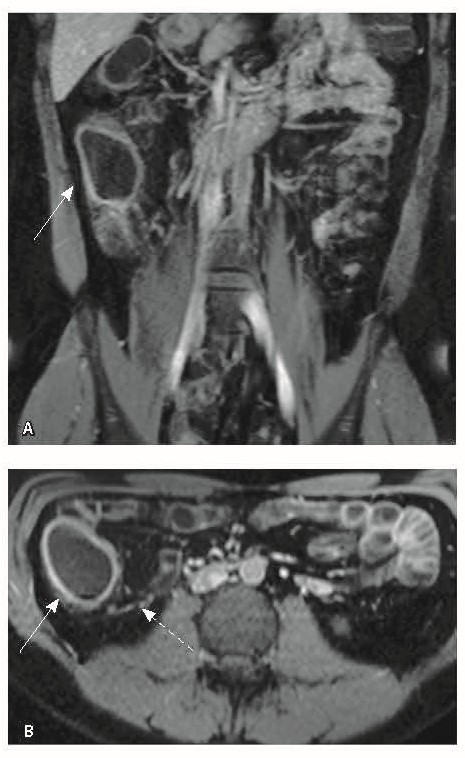

Назначена ГИБТ адалимумабом (препарат Хумира) по стандартной схеме 160 мг п/к (неделя 0), 80 мг п/к (неделя 2) с последующим плановым поддерживающим режимом 40 мг п/к каждые 2 недели. Через 9 месяцев установлена эндоскопическая ремиссия, однако сохранялась концентрация фекального кальпротектина более 2000 мкг/г. Через год жалобы возобновились, тогда же впервые была выявлена задняя анальная трещина. Выполнена магнитно-резонансная энтерография, обнаружены воспалительные изменения, характерные для БК (рис. 2 и 3).

Рис. 3. Магнитно-резонансная энтерография, Т1-взвешенное изображение после внутривенного контрастного усиления (гадобутрол, 5 мл): А – фронтальная проекция, Б – аксиальная проекция. Наблюдается выраженное усиление интенсивности сигнала от восходящего отдела ободочной кишки (стрелка), усиление сигнала от окружающей клетчатки (пунктирная стрелка)